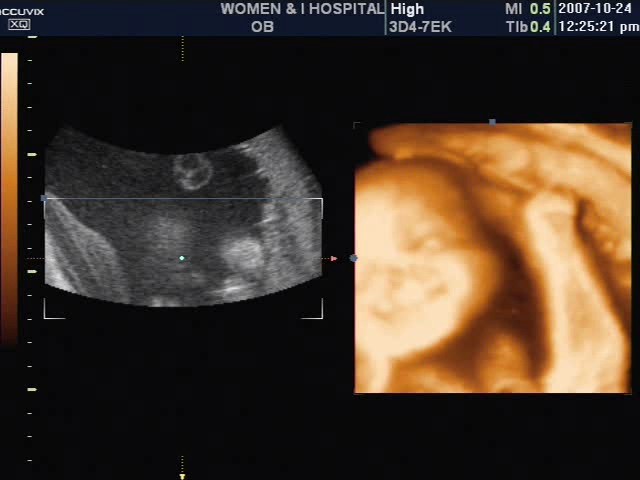

12월 17일 울 둥이들을 만날수 있게 됐어요.. 아들 둥이구요.. 36주에 몸무게가 2.7, 2.5 너무 건강하데요...